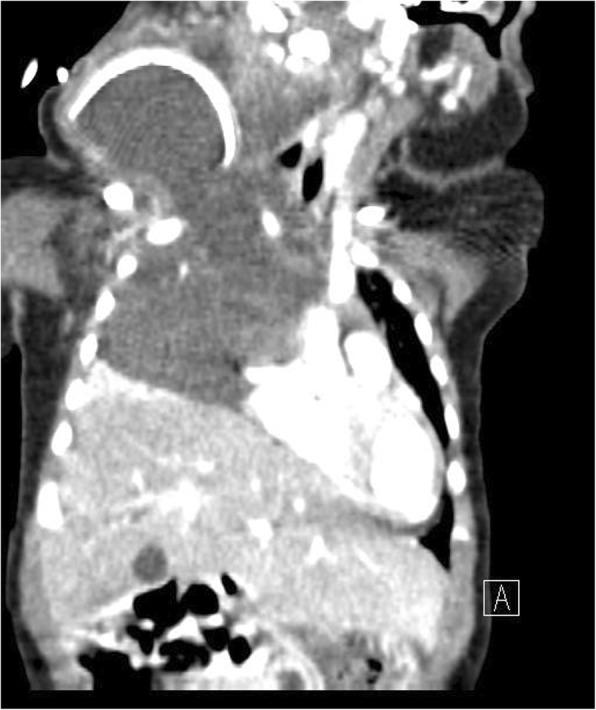

Lymphatic malformations are histologically benign vascular structures that vary in anatomic lesion and size. Extensive head and neck lymphatic malformations may be life-threatening. In the present study, we described three difficult-to-treat infants with giant cervico-mediastinal lymphatic malformations accompanied by severe respiratory distress.

Case 1. A Korean girl born at a gestational age of 37 weeks and weighing 2920 g had a large cervical mass compressing the trachea. Despite initial OK-432 sclerotherapy, the mass extended over the contralateral retropharyngeal space and mediastinum. Although the cervical mass was completely excised, our patient was not weaned off the ventilator. The mediastinal lymphatic malformation was excised, and our patient underwent continued intensive respiratory care with nasal continuous positive airway pressure for 6 months. She is now 5 years old and doing well without any sequelae. Case 2. A 5-month-old Korean boy showed respiratory difficulty with feeding intolerance after partial excision of a neck lymphatic malformation. We found that the remnant cervical mass had grown into the retropharyngeal space and mediastinum. After a second operation for the cervico-mediastinal mass, he experienced severe respiratory difficulty requiring ventilator care for 6 months. However, he died from central-line fungal sepsis. Case 3. A 30-day-old Korean girl was referred for remnant lymphatic malformation after partial excision. The cervical mass extended to the mediastinum and occupied half of the thoracic cavity, encasing all of the major vessels. After surgical excision, she underwent ventilator care and pleurodesis three times with doxycycline for recurrent pleural effusion. At the age of 26 months, she was weaned off supplementary oxygen and she showed normal development without any sequelae.

淋巴管畸形是组织学上良性的血管结构,其解剖病变和大小各不相同。广泛的头颈部淋巴管畸形可能危及生命。在本研究中,我们描述了三名患有巨大颈纵隔淋巴管畸形并伴有严重呼吸窘迫的难治性婴儿。

病例1。一名孕37周出生、体重2920克的韩国女孩,颈部有一个巨大肿块压迫气管。尽管最初进行了OK-432硬化治疗,但肿块扩展到对侧咽后间隙和纵隔。尽管颈部肿块被完全切除,但我们的患者仍未脱机。纵隔淋巴管畸形被切除,我们的患者接受了持续6个月的鼻持续气道正压通气强化呼吸护理。她现在5岁,情况良好,没有任何后遗症。病例2。一名5个月大的韩国男孩在颈部淋巴管畸形部分切除后出现呼吸困难和喂养不耐受。我们发现残留的颈部肿块已长入咽后间隙和纵隔。在对颈纵隔肿块进行第二次手术后,他出现了严重的呼吸困难,需要呼吸机护理6个月。然而,他死于中心静脉导管相关真菌败血症。病例3。一名30天大的韩国女孩因部分切除后残留淋巴管畸形前来就诊。颈部肿块延伸至纵隔,占据胸腔的一半,包绕所有主要血管。手术切除后,她因复发性胸腔积液接受了三次呼吸机护理和强力霉素胸膜固定术。在26个月大时,她停用了补充氧气,发育正常,没有任何后遗症。